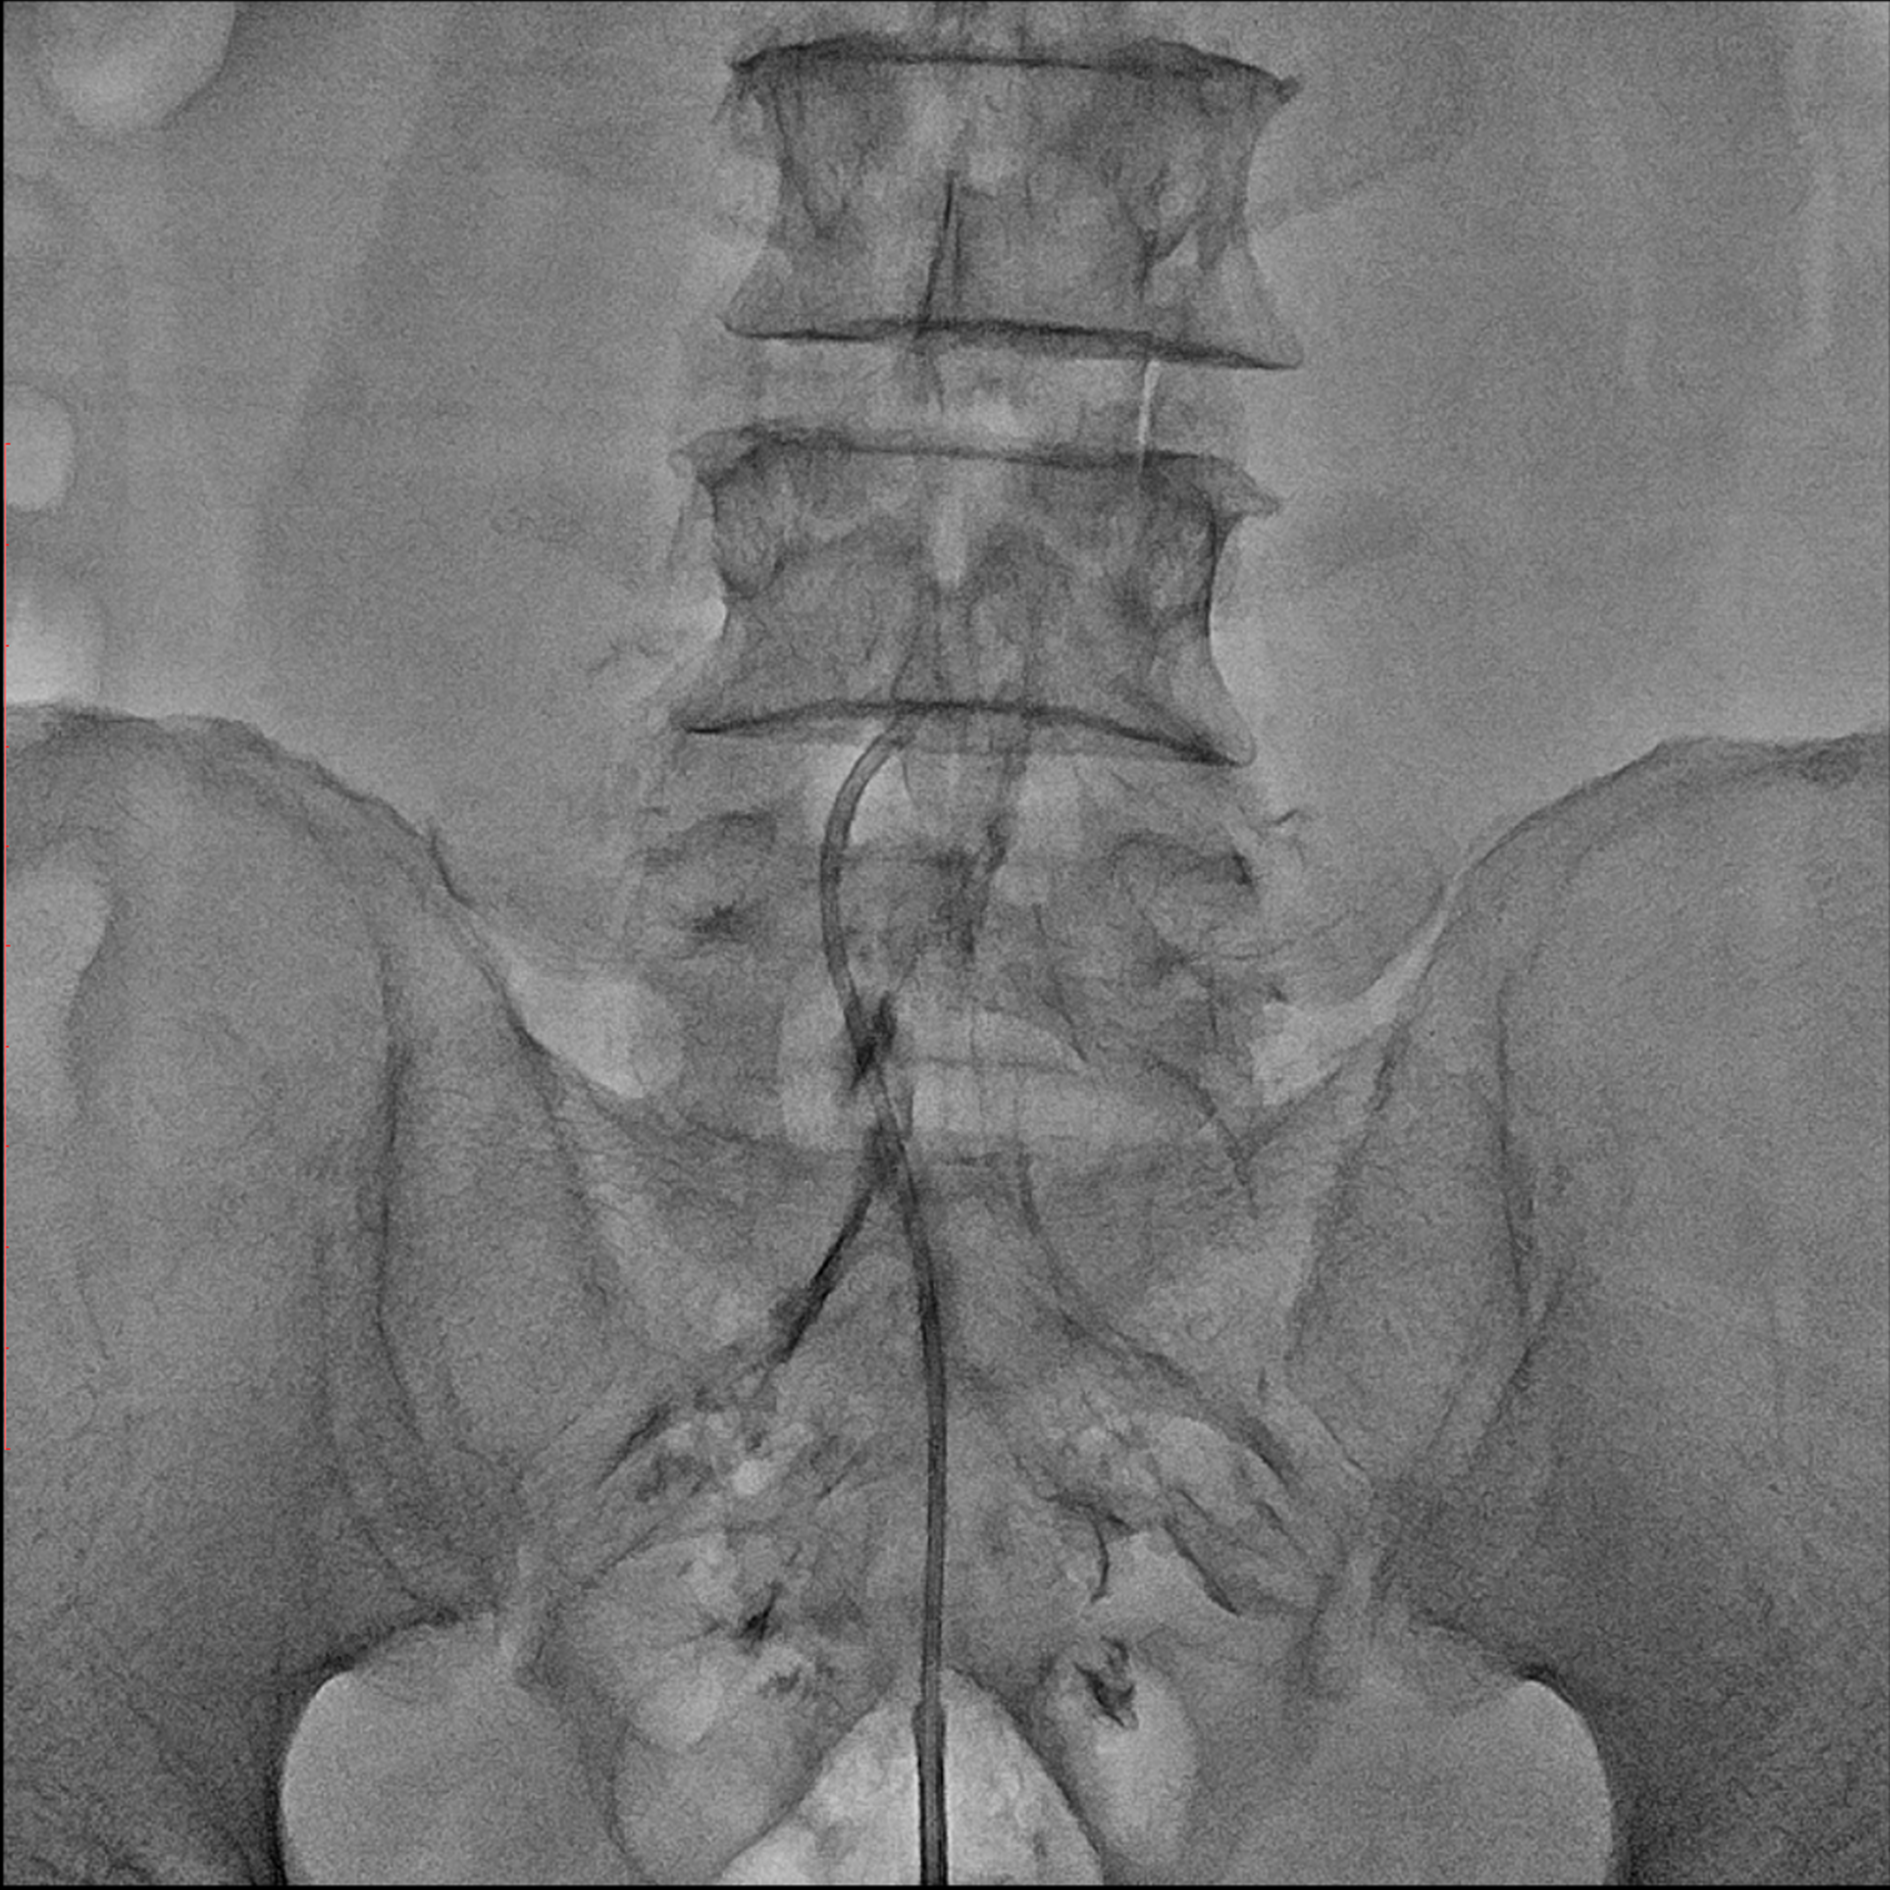

경막외 유착박리술, Epidural Neuroplasty